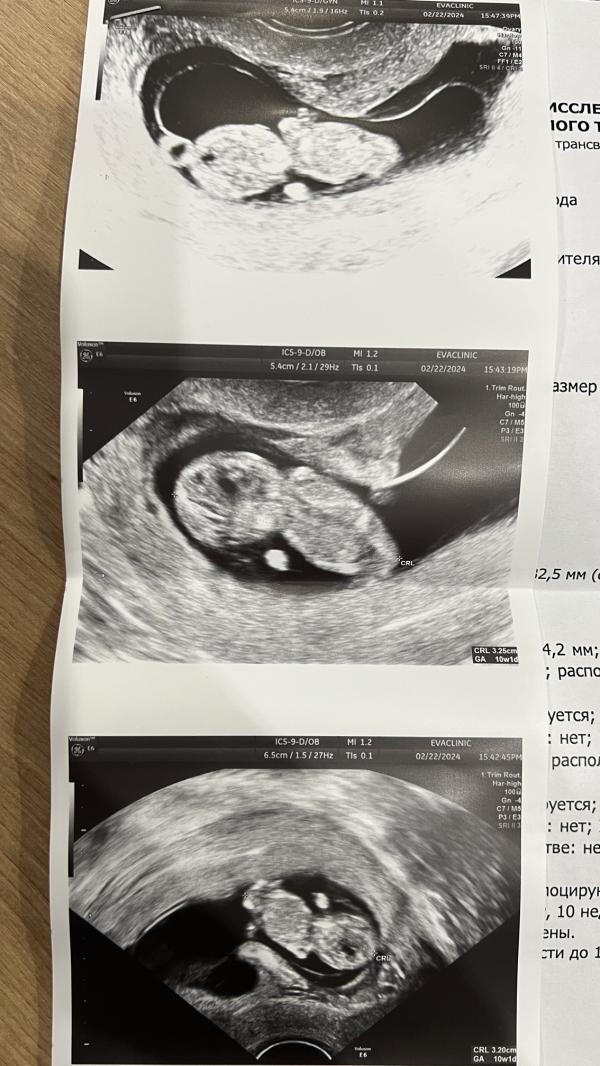

Девушки здравствуйте, подскажите пожалуйста почему может быть такой формы плодное яйцо? Болей и выделений никаких нет, ничего не беспокоит. Врач сказала, что в этом ничего такого нет, и места малышу предостаточно. Но мне все равно не спокойно #первыйпост

@mama_moom, ну явно же, что яйцо не такой формы должно быть) здесь банан, или форма сердца, но никак не яйцо

И тем более слова гинеколога, что форма интересная

В плодном яйце - эмбрион. Смущает, что форма странная, как сердце, или как банан. Сама гинеколог сказала: «какая интересная форма плодного яйца»

@boannbo это тонус матки. Сжало плодное яйцо. Ничего страшного, это не редкость